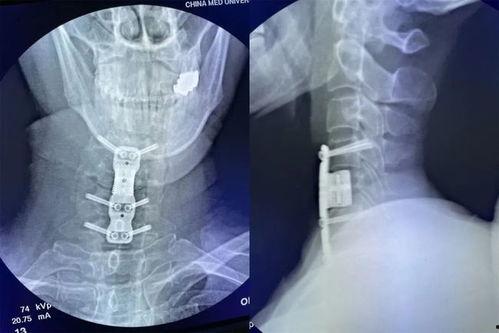

6. 植入人工椎间盘或椎体

为了恢复颈椎的稳定性,医生会在切除病变组织后,植入人工椎间盘或椎体。这些植入物可以模拟正常椎间盘的功能,减轻颈椎的压力。

手术完成后,医生会逐层缝合切口,并包扎。术后,患者会进入恢复室,接受医生的观察和护理。